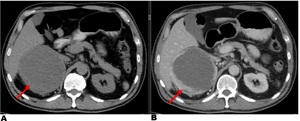

Given the patient’s clinical presentation, an abdominal ultrasound was conducted, revealing a suprarenal mass that warranted further investigation for potential adrenal involvement. Following the ultrasound, an abdominal CT scan was performed, showing a solid tumor that was rounded in shape, with lobulated edges and dimensions of 10cm in the right adrenal gland (Fig. 1).